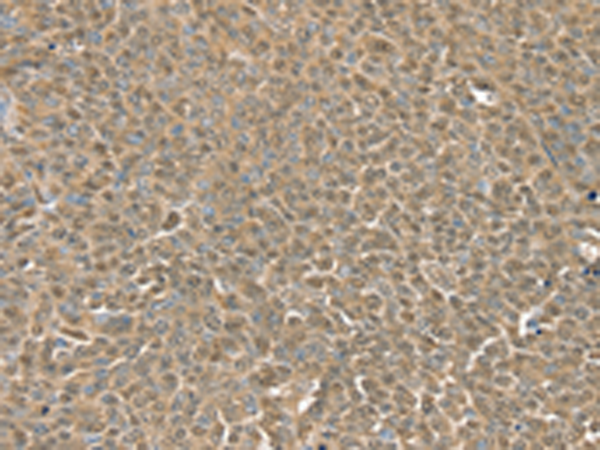

分类: 科研抗体货号: P08692别名: RGP4; SCZD9应用: IHC反应种属: Human, Mouse, Rat